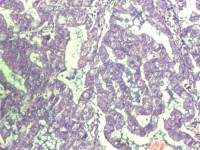

性别

女

年龄

55岁

临床诊断

异常子宫出血

一般病史

阴道不规则出血1月

标本名称

子宫内膜

大体所见

灰白色组织1堆、4*3.4*2.2CM大。

能诊断癌吗

子宫内膜样腺癌